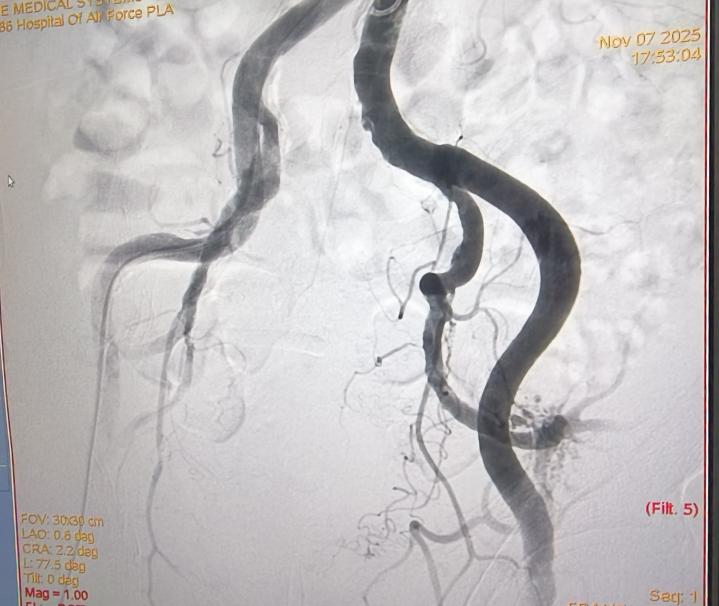

术前 术后

11月7日下午,手术正式进行,全程在患者清醒状态下完成,痛苦小,术后仅需对穿刺点进行加压包扎,恢复迅速。术后第二天,李老先生即可下床活动,身体恢复良好,目前已康复出院。